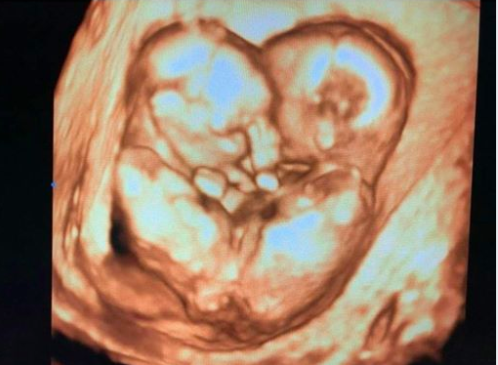

17/07/2020 03:33Kế hoạch tiếp theo với cặp song sinh dính liền hiếm gặp vừa được tách thành công

Chiều 16/7, đại diện Bệnh viện Nhi đồng Thành phố HCM, cho biết cặp chị em gái song sinh dính liền Diệu Nhi - Trúc Nhi đã hồi tỉnh, các chỉ số sinh hiệu đều ổn định. Tới sáng nay, hai em chỉ sốt nhẹ do viêm sau mổ, là phản ứng cơ thể bình thường.

"Cứ 12 tiếng đồng hồ, các bác sĩ sẽ họp giao ban tình hình sức khỏe hai bé Trúc Nhi - Diệu Nhi" - đại diện Bệnh viện cho hay. Hai em bé đặc biệt sẽ còn phải được theo dõi rất sát.

TS.BS Trương Quang Định - Giám đốc Bệnh viện Nhi đồng thành phố, cho rằng ca mổ đã thành công bước đầu, quá trình hồi sức và hồi phục của hai bé là chặng đường dài.

Các bác sĩ cho hay trong vòng 3 tháng tới, các bé sẽ được tái tạo đường tiêu hóa, đường tiết niệu, khép lại khung chậu...

Trước đó, sau khi hoàn thành ca mổ tách dính cực kỳ phức tạp, hai bé Trúc Nhi - Diệu Nhi được chuyển đến phòng hồi sức ngoại, được chăm sóc đặc biệt.

5h30 ngày 15/7, Trúc Nhi - Diệu Nhi được điều dưỡng chuyển từ khoa Sơ sinh đến phòng Phẫu thuật - Gây mê hồi sức. Gần 100 thầy thuốc của rất nhiều bệnh viện, chia thành nhiều kíp, sẽ giúp hai bé tách rời nhau sau 13 tháng sống cảnh dính liền vùng chậu bụng.

9h51, TS.BS Trương Quang Định, Giám đốc Bệnh viện Nhi đồng TP HCM, Trưởng ê-kíp mổ, rạch đường đầu tiên bắt đầu cuộc mổ. Sau đó, TS Trần Văn Dương, Bệnh viện Chợ Rẫy, Trưởng nhóm phẫu thuật tạo hình, bắt đầu rạch da, cân cơ, mở bụng tách 2 bé.

14h07, các bác sĩ đã tách thành công hai bé song sinh dính liền.

Sau khi tách rời, bé Trúc Nhi được chuyển sang phòng mổ siêu sạch số 12. Bé Diệu Nhi vẫn ở phòng mổ ban đầu. Ê-kíp chia thành 2 nhóm nhỏ, tiến hành phẫu thuật chỉnh - tạo hình cho từng bệnh nhi.

Hai bé được khép lại xương cánh chậu, khớp mu, tạo hình niệu sinh dục, mở hậu môn tạm và đóng cân cơ, da.

18h40, các bác sĩ đã hoàn thành bó bột cho Trúc Nhi. 19h25, Diệu Nhi đã được đưa ra khỏi phòng mổ sau khi các bác sĩ hoàn tất khâu tạo hình cuối cùng, khâu vết mổ, bó bột. TS Trương Công Định cho hay: "Ca mổ kết thúc thành công”.